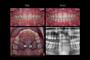

326-Affollamento dentale

Affollamento dentale